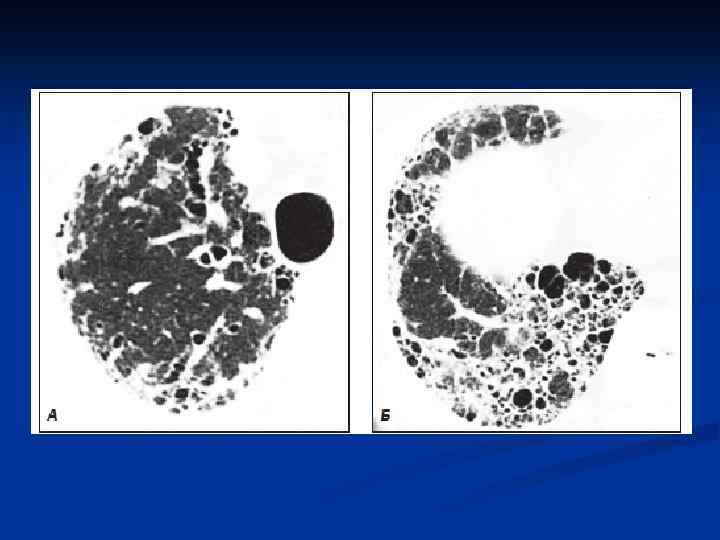

Различают 5 степеней патоморфологических изменений в легочной ткани у больных идиопатическим фиброзирующим альвеолитом: n n n I степень: отек межальвеолярпых перегородок, клеточная инфильтрация, извилистость капилляров. II степень: экссудация серозно-фиброзной жидкости (богатой белком и окрашивающейся эозином) и клеточная экссудация в альвеолы, что приводит к облитерации альвеолярного пространства (внутриальвеолярный фиброз). Другой путь организации альвеолярного экссудата - резорбция его в межальвеолярные перегородки с уплотнением и фиброзом последних. Оба эти варианта могут сосуществовать. III степень: вовлечение в процесс бронхиол с образованием мелких кист и разрушением структуры альвеол. IV степень: нормальная структура легочной ткани полностью нарушается, кистозные полости постепенно увеличиваются. V степень: образование так называемого «сотового (или ячеистого) легкого» . Кисты достигают 1 см в диаметре.